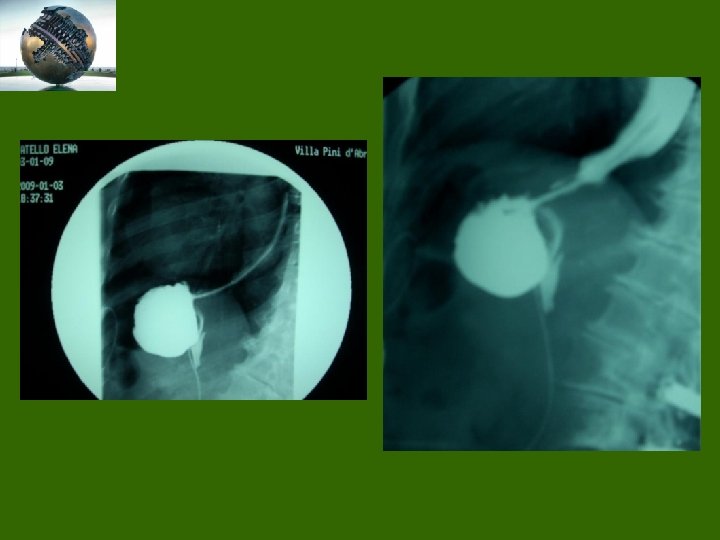

Palloncino intragastrico (BIB) PIRTI endog. Ast

Slippage

Controllo post-operatorio

Erosione/Migrazione